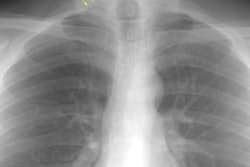

Hodgkins lymphoma developing in a patient with sarcoid:

The film below was from 1997. The right paratracheal mass has enlarged markedly in comparison to the patients old film. This finding was felt to be atypical for sarcoid and a CT was performed. The CT scan demonstrated a large anterior mediastinal/right paratracheal mass which severely compressed the superior vena cava, coupled with mediastinal and subcarinal adenopathy. (Click here to view CT scan). Mediastinoscopy was performed and the patient was discovered to have Hodgkins lymphoma.